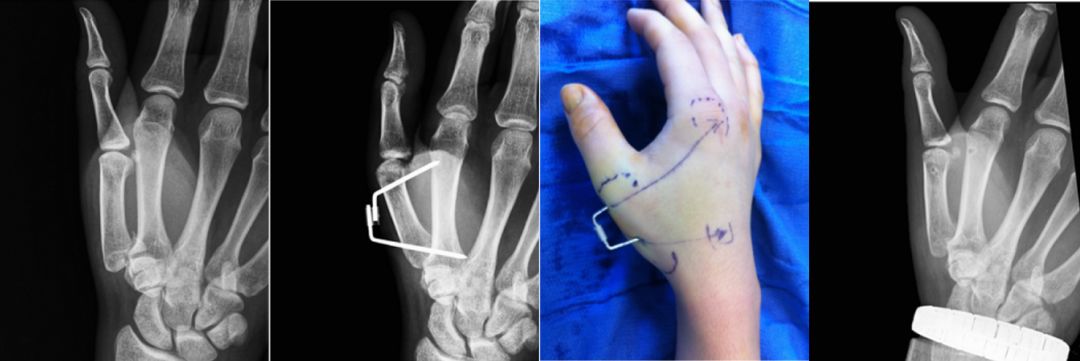

2008年来自美国的学者Ruland在J Hand Surg上报道了应用克氏针制成的动态外固定支架治疗不稳定型近节指间关节骨折脱位和pilon性损伤。

2014年Tech Hand Surg报道了日本学者Mohamed Adi将Iselin技术进行改良,闭合复位骨折,经皮穿针并将克氏针在外部锁定,用来治疗Bennett骨折。